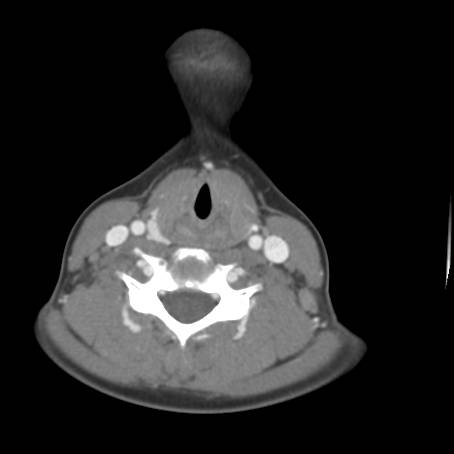

![]() Figure 5d |

Describe CT.